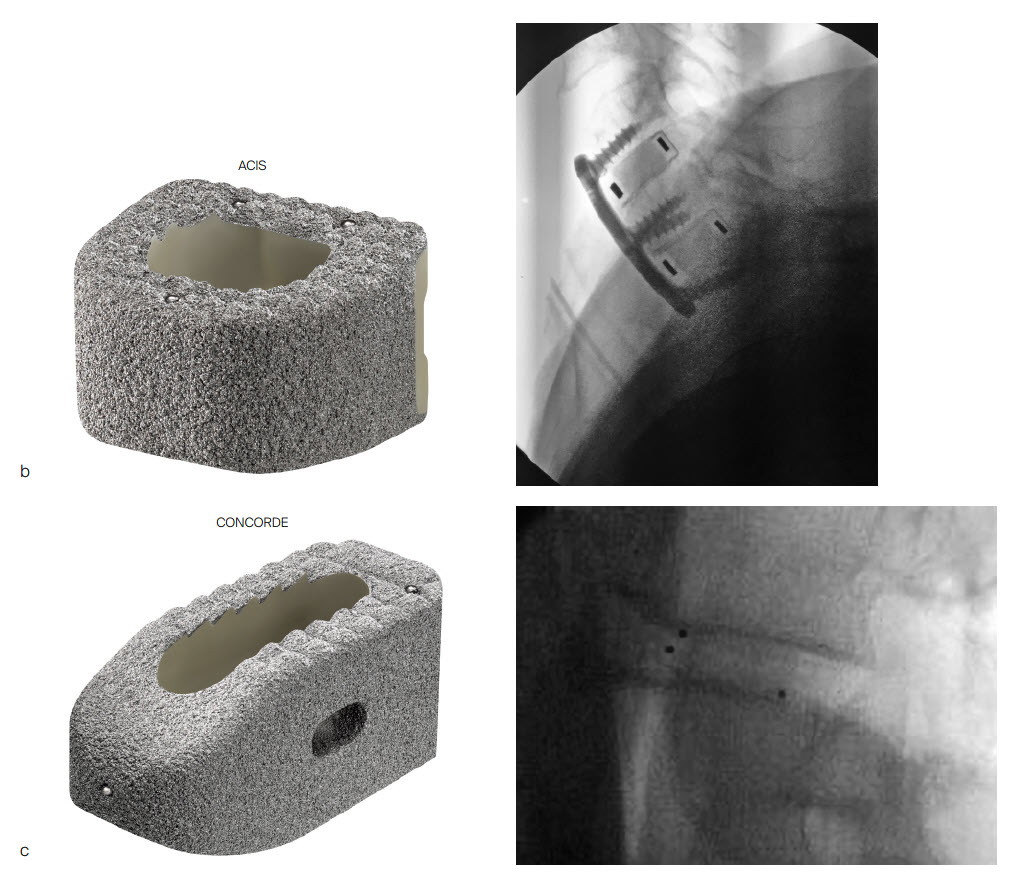

The PEEK core of the PROTI 360° cage has favorable imaging characteristics which support the postoperative assessment of fusion, while the titanium outer layer allows measurement of cage positioning. Clinically, depending on the image quality, plane of view, and patient anatomy, the PROTI 360° cage may show a ghost image of the entire cage on fluoroscopic images (Fig 7). CT images show minimal scatter around the implant (Fig 8).

The PROTI 360 cages are available as sterile implants and are compatible with ACIS System (Fig 9a), T-PAL Interbody System (Fig 9c) and CONCORDE Bullet (Fig 9c) instrument sets. The ACIS implants are available in 5-10mm heights, in Lordotic Small, Standard, and Large designs and in Parallel Standard or Convex Standard. The CONCORDE implants are available in Parallel and Lordotic designs (7-15 mm heights, 23 and 27 mm lengths). The T-PAL implants are available in the High Curve design (7-15 mm heights, 10 x 28, 12 x 32 footprints).